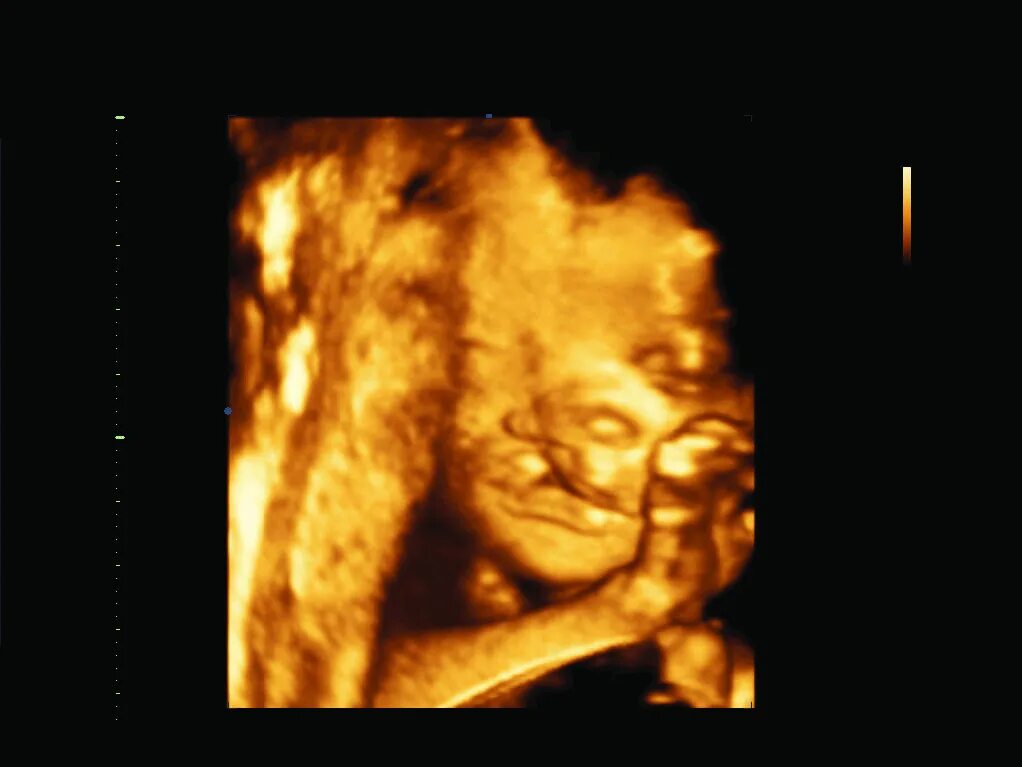

На каком сроке делают третий скрининг беременности